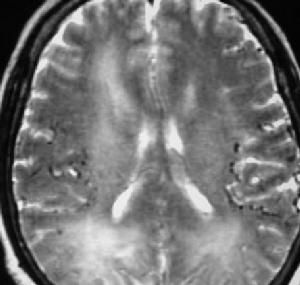

包括神經學檢查,電腦斷層掃描(多數情況下沒有對比增強)或核磁共振,都卜勒超聲和造影,主要靠臨床症狀,輔以成像技術。成像技術也可幫助確定卒中的亞型和原因。此外血液測試也可以幫助診斷。